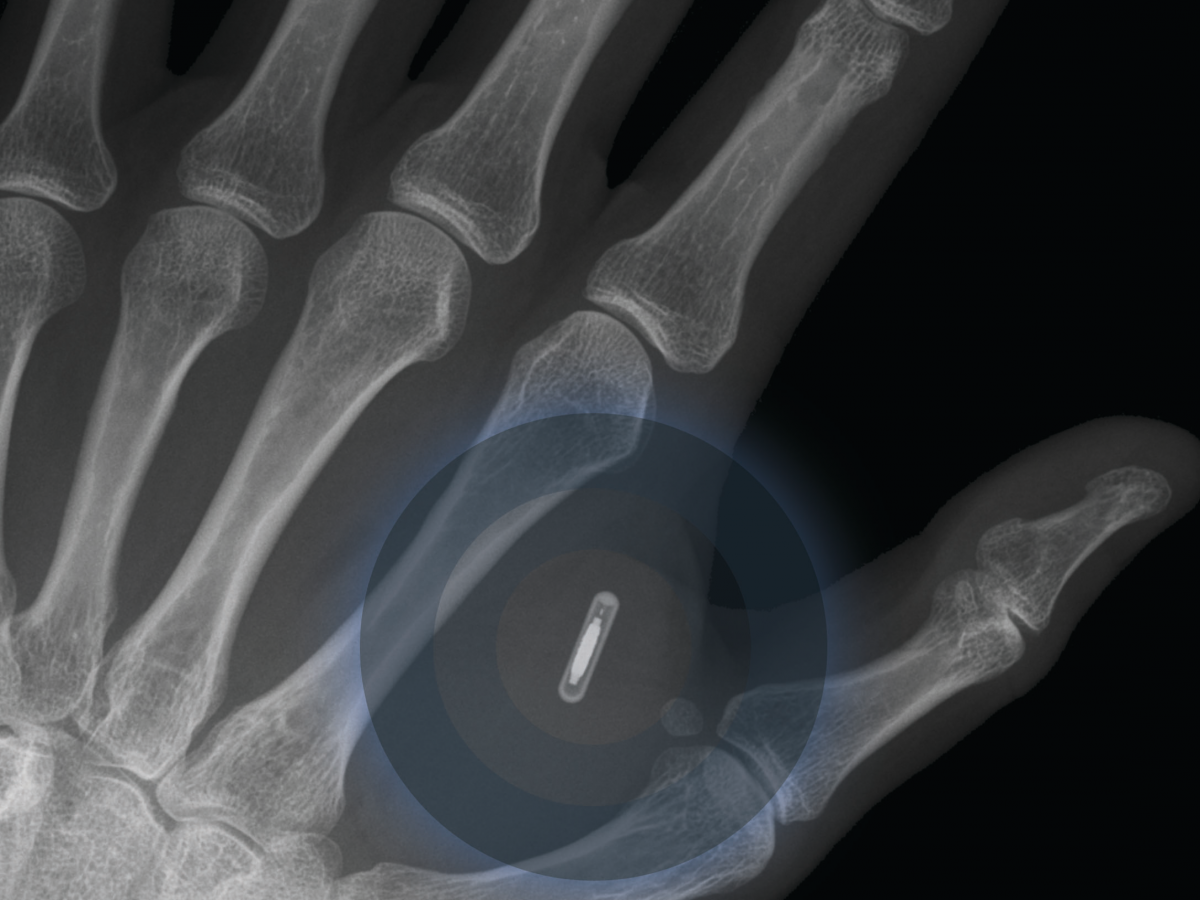

В 2025 году попадет на рынок первый имплантируемый мобильный телефон

Примерно в 2023 году фраза «я привязан к своему телефону» зазвучит совсем по-новому.

Примерно 80% опрошенных утверждают, что на рынок выйдет в ближайшие 7 лет первый имплантируемый мобильный телефон. Доклад рассказывает, что ожидается, что подобное устройство сумеет точнее следить за состоянием здоровья владельца, и кроме того позволит абонентам общаться, используя мозговые сигналы или радиосигналы вместо вербальных средств. Такие имплантируемые медицинские устройства, как слуховые аппараты и кардиостимуляторы, уже стали для нас совершенно привычными. И, кажется, что к 2025 года на наших глазах будет происходить все более активное распространение имплантируемых технологий.